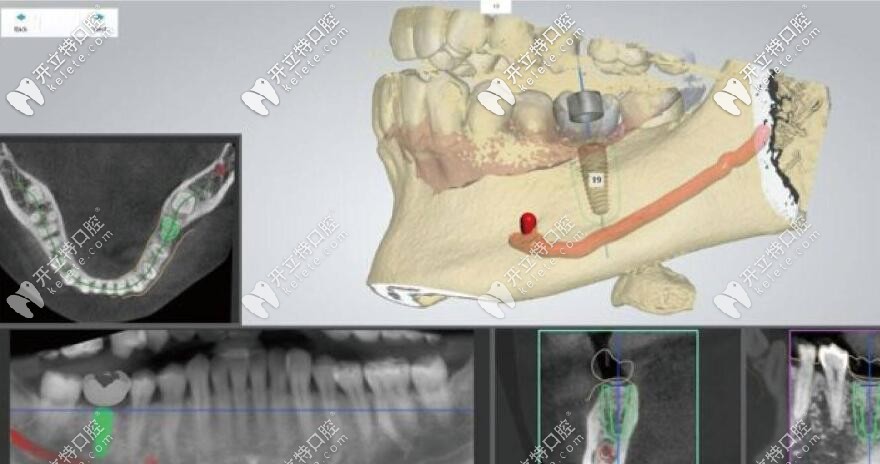

1、運用數(shù)字化3D導(dǎo)板技術(shù),制定種植方案:以微創(chuàng)為主導(dǎo),形成全頭顱360°影像;

2、通過CAD/CAM激光掃描和CBCT等,在計算機上重建患者口腔三維立體模型,有效掌握顧客的組織結(jié)構(gòu),清楚還原牙神經(jīng)和血管的位置。

3、由3D打印技術(shù)制作的種植導(dǎo)板,對手術(shù)全程的精準(zhǔn)把控,設(shè)定種植位置能有效避開牙組織損傷和牙神經(jīng)位置,極大限度減少手術(shù)時間及手術(shù)創(chuàng)傷,實現(xiàn)手術(shù)方案。